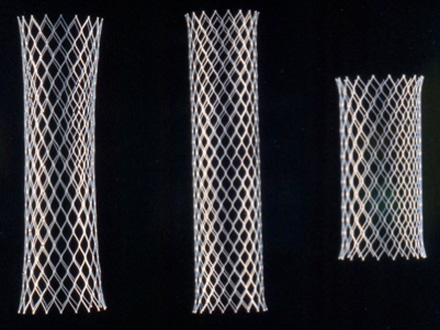

Types of metallic stents.